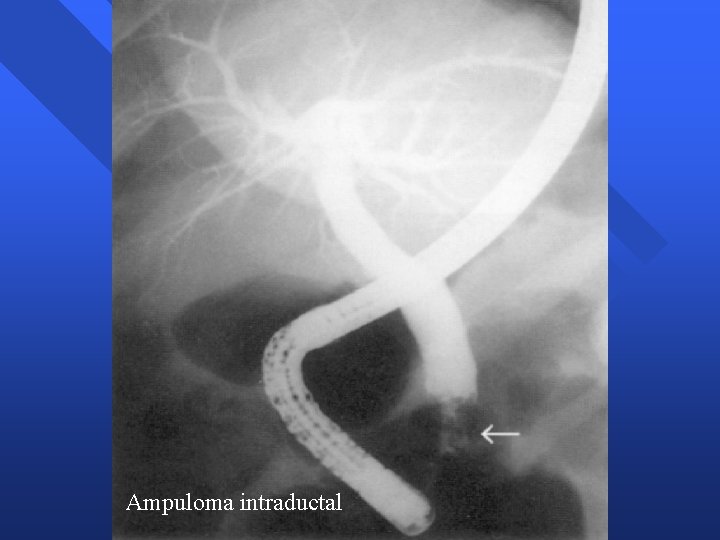

Tumores Ampolla Vater Ampuloma n Apariencia endoscópica – – – Papila mayor aumentada de tamaño Impronta suprapapilar colédoco distal dilatado Mucosa normal » Ampuloma intraductal – Mucosa neoplásica » Nodular, irregular, friable, ulcerada n Apariencia radiológica – Colédoco y conducto pancreático dilatados – Retraso evacuación drenaje – Estenosis distal / defecto repleción distal

Ampuloma intraductal